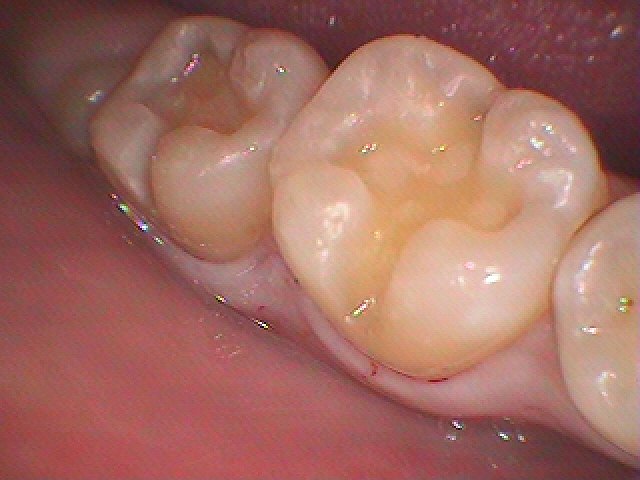

右下の奥歯

CR樹脂にて修復すると摩耗して段ができます

しっかりと強度のあるセラミックにて修復しています